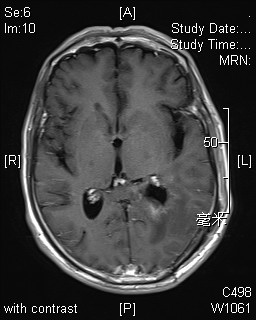

患者男性,62岁,因“反复头晕半月余”入院,颅脑MRI提示:左侧侧脑室肿瘤伴脑室周围脑水肿。肿瘤大小约5*4*4厘米。

神经外科竺国充副主任医师和徐震主治医师,术前仔细研究影像学资料,分析肿瘤准确位置、大小及血供情况。考虑肿瘤位于优势半球,选择最适手术入路。2014年7月2日在麻醉科胡弘毅医师及手术室护士配合下为患者成功施行了手术。术中见肿瘤占据侧脑室三角部及体部、与丘脑及脉络丛组织粘连紧密。部分突入颞角,比邻脑干。竺国充和徐震医师在显微镜下仔细分离,历时5个小时,终于将患者脑室内肿瘤完全切除,脑脊液通路完全打通,术后复查MRI未见肿瘤信号,脑室形态恢复正常。术后病理结果为透明细胞室管膜瘤,术后患者未遗留神经功能障碍。

术前MRI 术后MRI